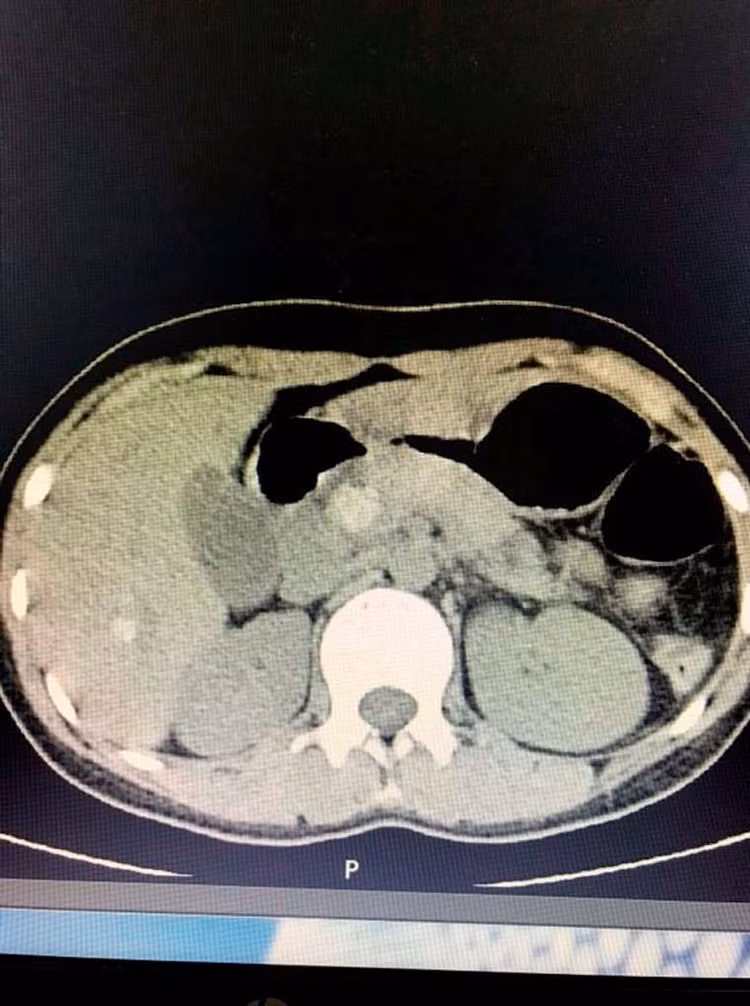

Sau khi được siêu âm và chụp cắt lớp, cho thấy hình ảnh sỏi ống mật chủ và sỏi đường mật trong gan phải. Người bệnh nhanh chóng được điều trị nội khoa, hồi sức tích cực và chỉ định phẫu thuật mở ống mật chủ lấy sỏi, nội soi đường mật tán sỏi điện thủy lực.

Theo ThS.BS Trần Thanh Tùng  - Phó trưởng Đơn vị Ngoại – Trung tâm KCB CLC, người trực tiếp thực hiện ca phẫu thuật cho biết: Đây là một trong những trường hợp phẫu thuật khó vì sỏi trong gan và sỏi ống mật chủ kích thước tương đối to, đường kính khoảng 2cm nằm kẹt chặt tại vị trí Oddi, không thể lấy sỏi bằng phương pháp thông thường. Các bác sĩ đã phải phẫu thuật mở ống mật chủ lấy sỏi kết hợp với nội soi đường mật tán sỏi điện thủy lực giúp tán nhỏ viên sỏi, thu nhỏ kích thước để lấy sỏi ra ngoài đồng thời không làm tổn thương cơ Oddi.

Viên sỏi to kẹt chặt tại vị trí Oddi